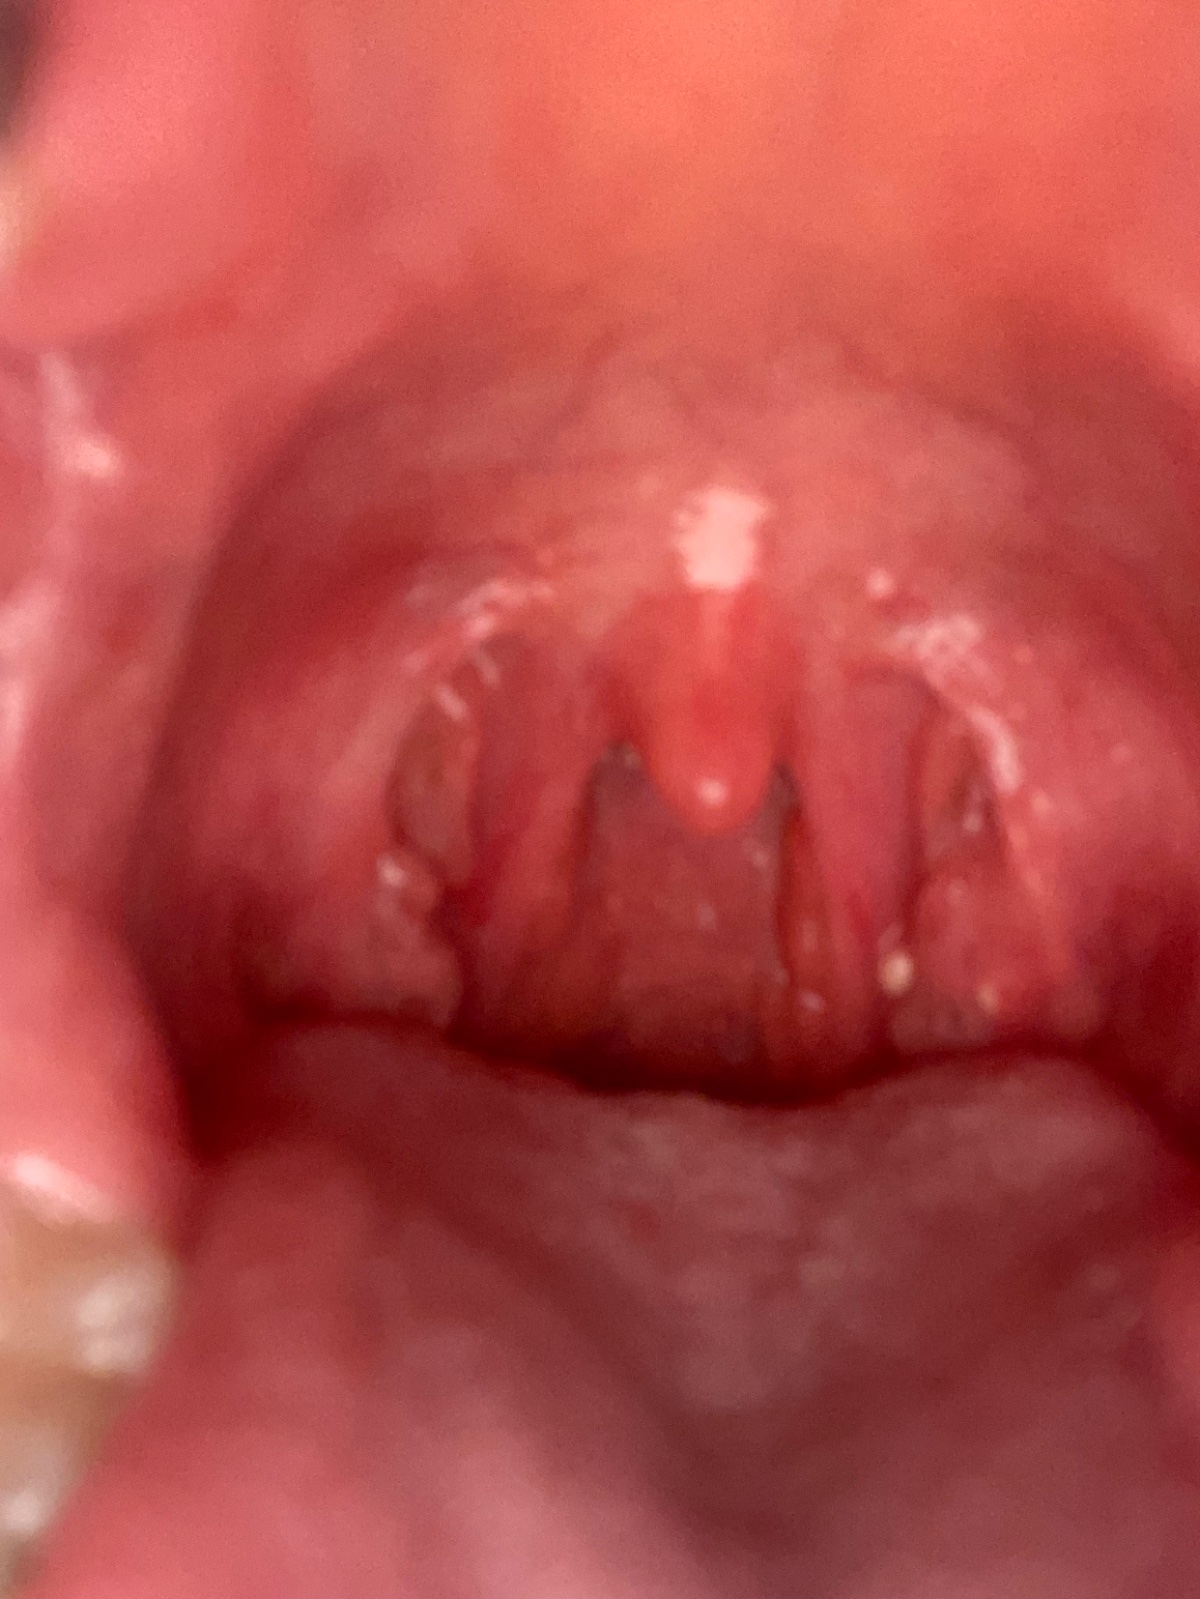

Dobrý deň, nemáte niekto skúsenosť, či ide o začínajúcu angínu? Tvoria sa mi biele fľaky na mandliach, pribúdajú…hrdlo ma dosť začína bolieť a stupňuje sa to. Hlava a oči ma tiež bolia a som neskutočne unavená. Samozrejme že ak sa mi to zhorší pôjdem k lekárovi, len sa chcem opýtať či s tým niekto nemal skúsenosť. Ďakujem 🙂

@zuzkamrkva21 ano toto vypada na anginu ,streptokoka,pomaha kloktanie slanou vodou a to aj 5x denne. Antibiotika ti musia sadnut,inak sa to vracia.idealne donutit doktorku k steru.

Ak sa ti aj zle prehĺta tak to bude angína